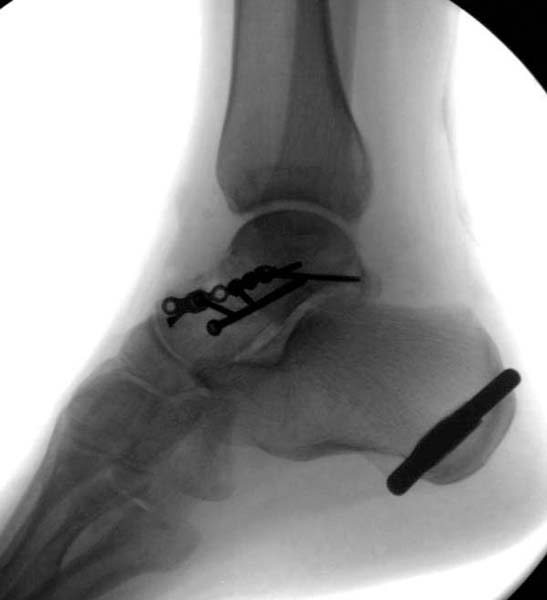

> Больная стабильная после хирургических мероприятии и получив добро,

> приступили к закрытому вправлению таранной кости с укладкой наружного

> фиксатора. Затем укладка больную на бок и открытый остеосинтез

> После спадения отека на стопе произведена фиксация тарана. Кстати, коллеги

> пересмотрели первоначальную консультацию по позвоночнику и на двух уровнях